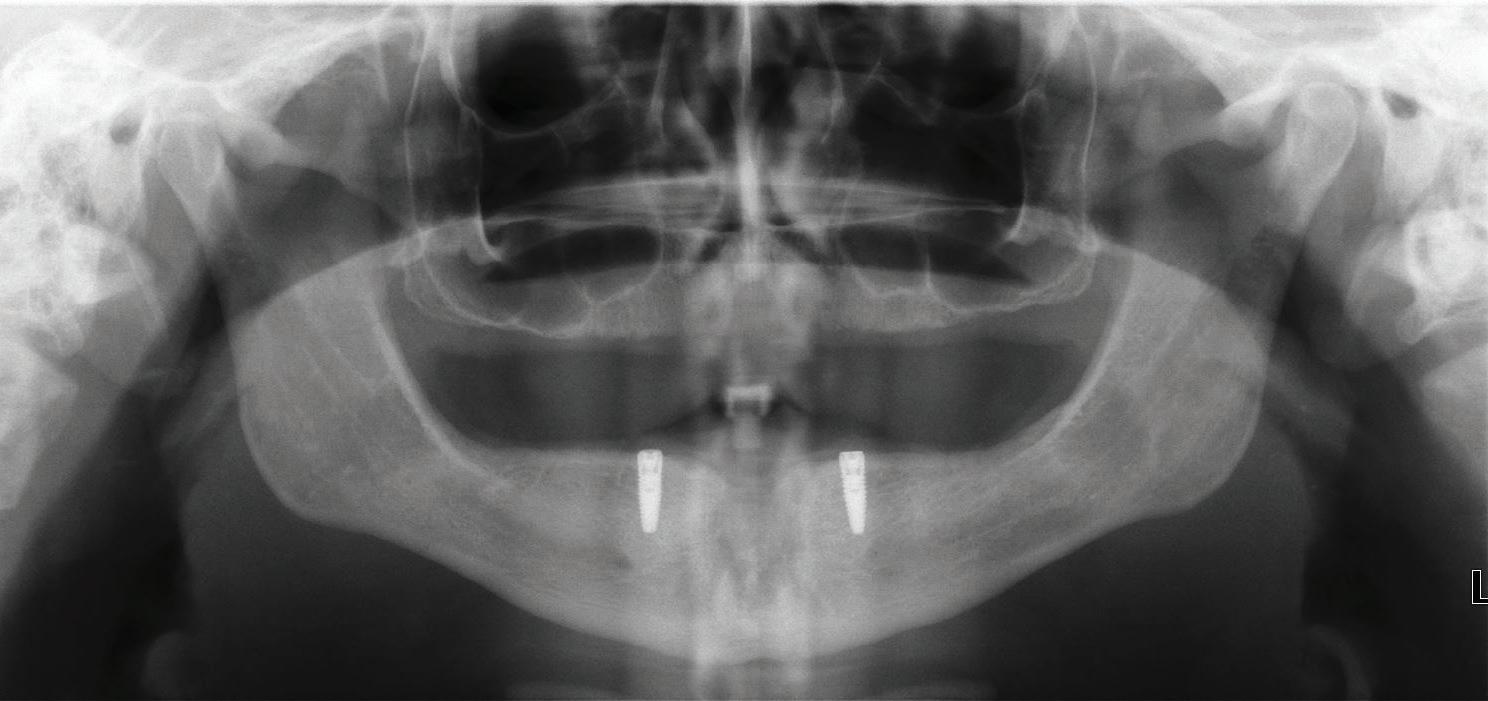

Implants were placed in areas of nos. 22 and 27. Implant no. 22 was Nobel Replace RP 4.3x11.5 torqued to 42.1 N/cm; implant no. 27 was Nobel Replace RP 4.3x11.5 torqued to 45.0 N/cm. Due to the patient wearing dentures, cover screws were placed and horizontal mattress sutures were placed. (The ends were clipped after the photos.) The patient was seen two days after and was healing well He was very happy with his treatment.